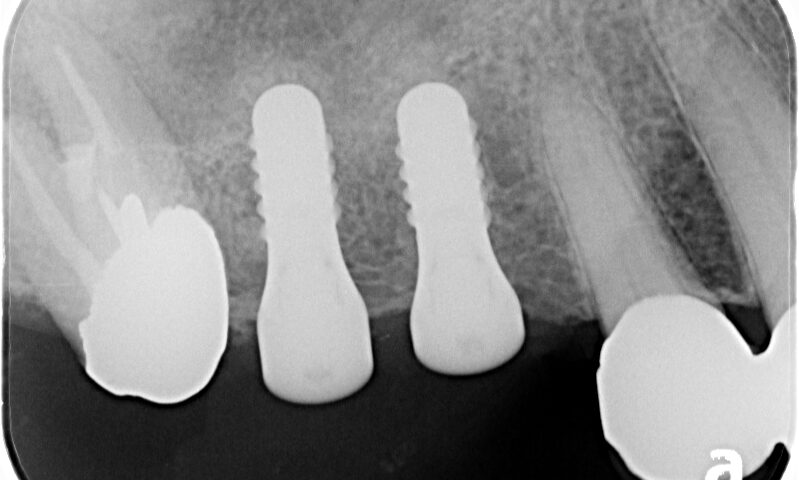

コンピュータガイドでしっかり位置決めを行います。やや上顎洞にかかるのでソケットリフトという手術を併用しました

しっかりと歯が入りました。その後右下も希望されたため右下にもインプラントを行いました。